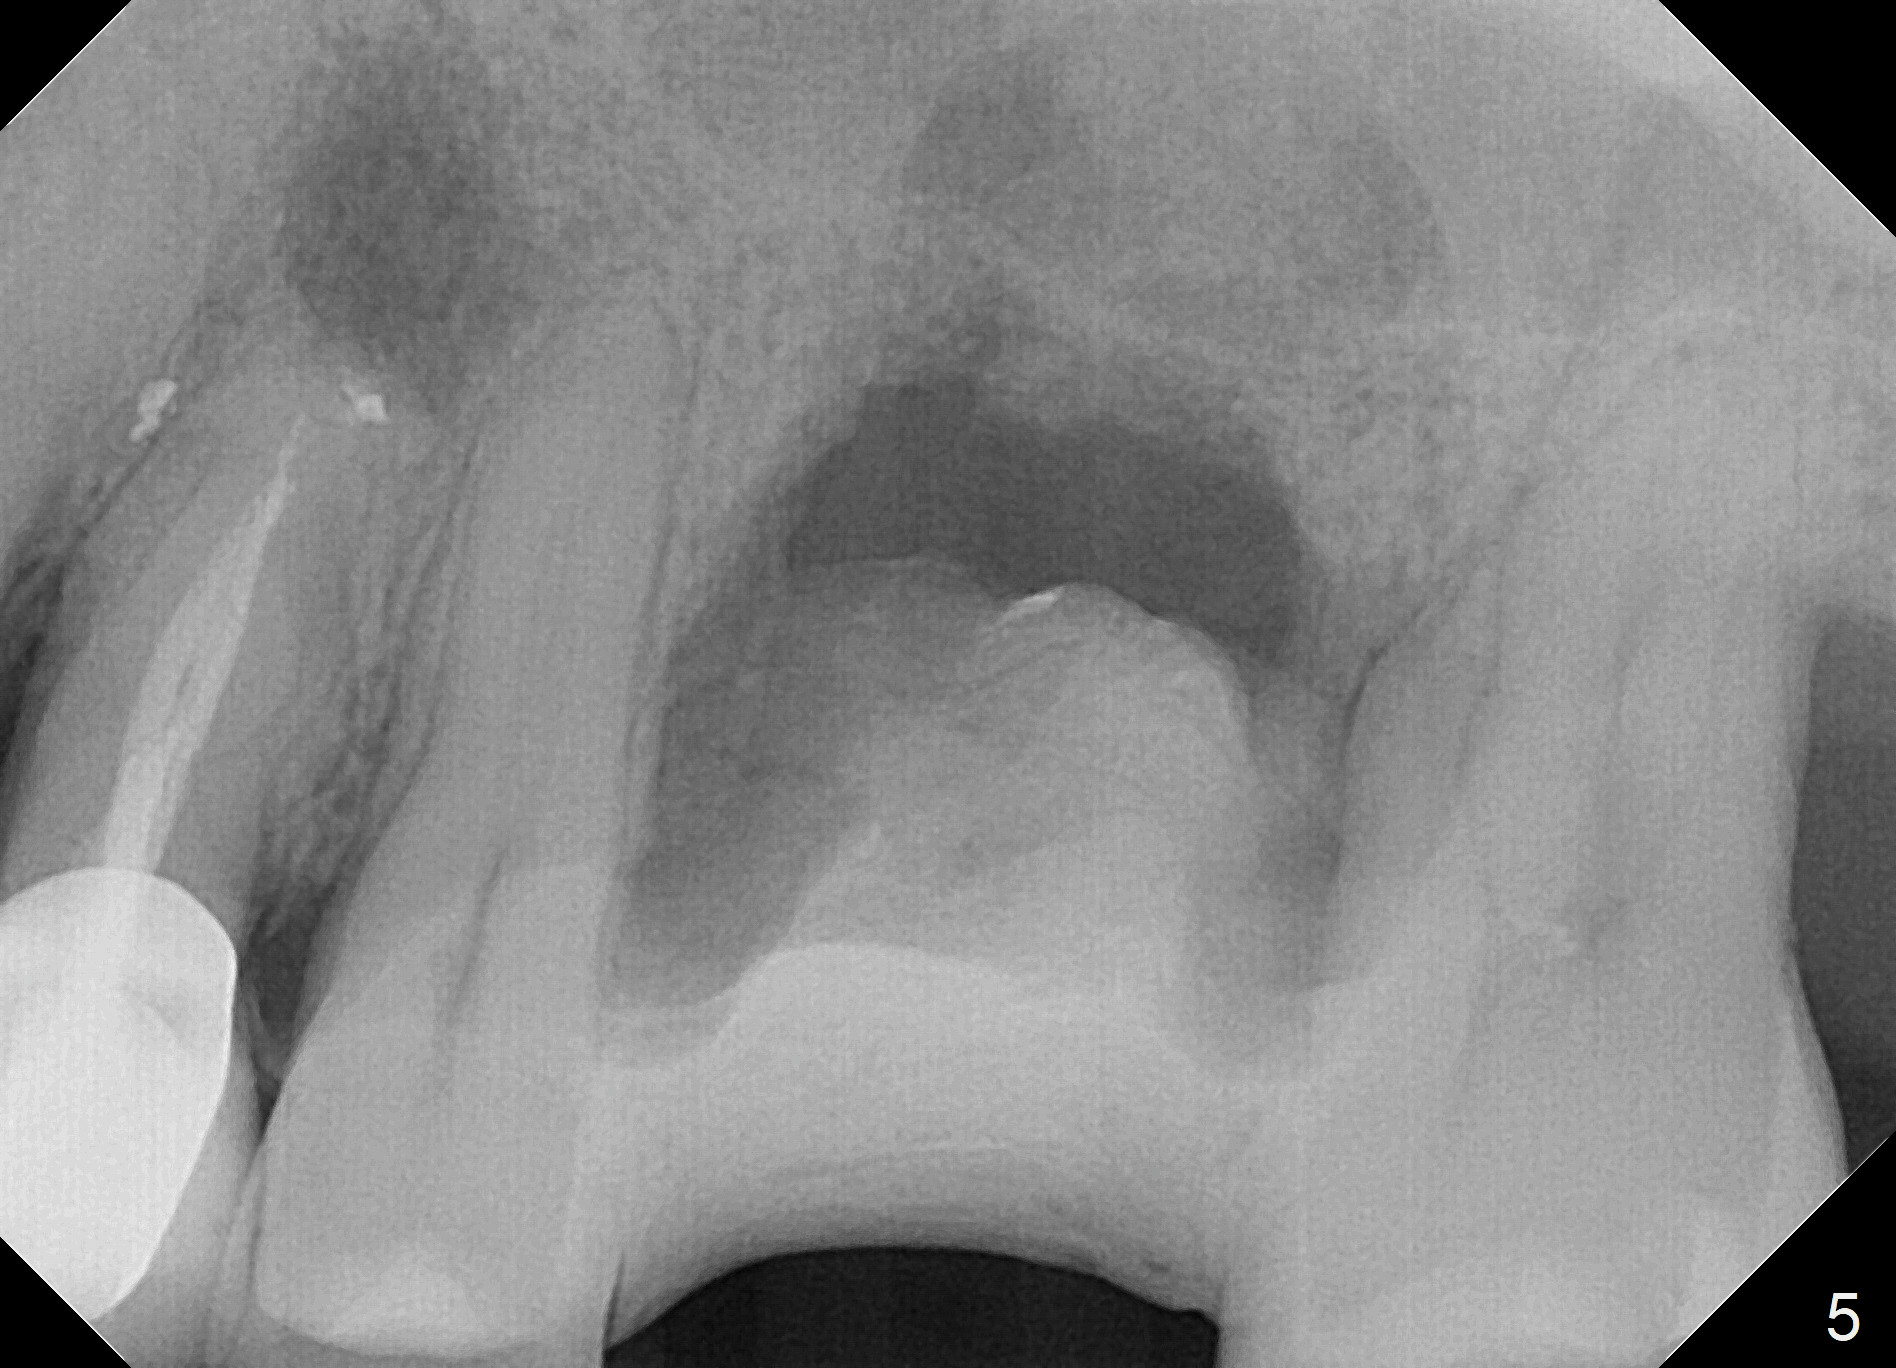

Failed Placement Due to Insufficient Thread Engagement

When the tooth #14 is extracted, the buccal plate is lost, while the apex of the palatal socket is perforated. The palatal slope of the septum appears to be a suitable site for osteotomy, but the depth seems to be 2 mm. After sequential osteotomy until 5.3 mm with drills, a 5.9 mm SM tap obtains stability (Fig.2). A 5.9x8 mmm implant is placed with barely sufficient stability after 1 piece of PRF membrane and VeraGraft (Fig.2-4). The implant rotates and dislodges when an abutment is being placed. Neither do 6-8x17 mm Tatum taps achieve primary stability. Socket preservation is performed, followed by periodontal dressing (Fig.5). Primary stability might have been obtained if a smaller IBS implant with fins were placed in the palatal socket. The periodontal dressing has dislodged 1 week postop; the socket appears healing (Fig.6,7). Bone graft seems to be minimal or bone density of the graft is low (Fig.8). The socket heals with a wide ridge 2 months post socket preservation, but the tooth #15 seems to be buccal (Fig.9) and mesial (Fig.10) shift. After use of Magic Split and Expanders (until 3.8 mm for 13 mm), try 5 mm dummy implant (Fig.11). If 6 mm one fails to achieve stability substantially, switch to 7 mm Tatum tapered tap provided there is enough mesiodistal space (use 8 mm implant positioner to gauze the space beforehand (preop)). Consider using Vanilla (not Vera) Graft to fill in the gap between implant and osteotomy. When primary stability is obtained, place a nonfunctional provisional to prevent further shifting (Fig.11 white outline). After osteointegration, use the provisional (reline and separator) to distalize the tooth #15.